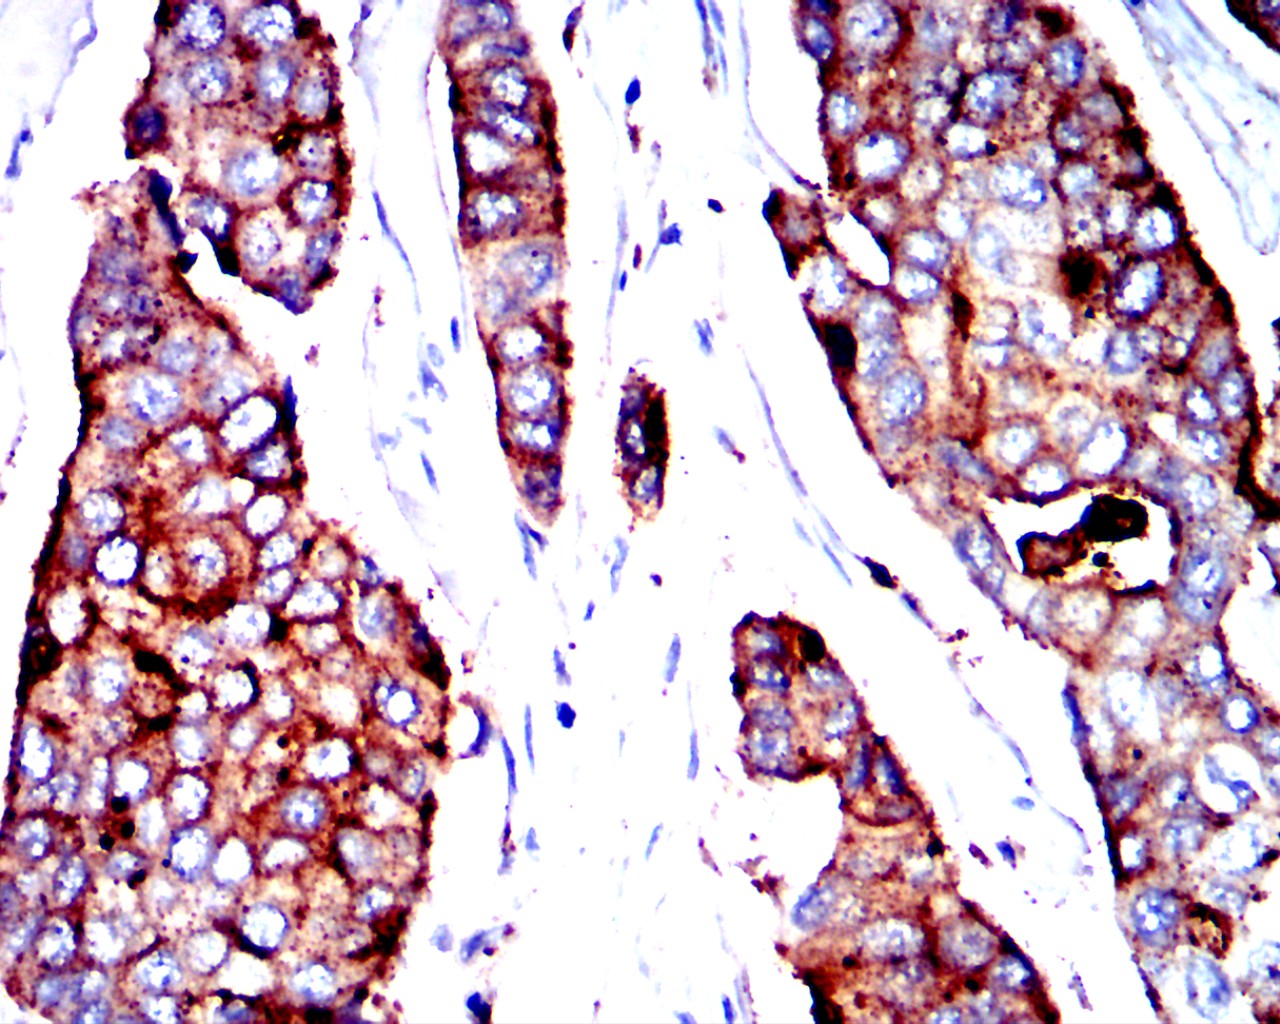

分类: 科研抗体货号: 32424别名: DPA1; PLT1; HLADP; HLASB; DP(W3); DP(W4); HLA-DPA; HLA-DP1A; HLA-DPB1应用: WB,IHC,FCM反应种属: Human